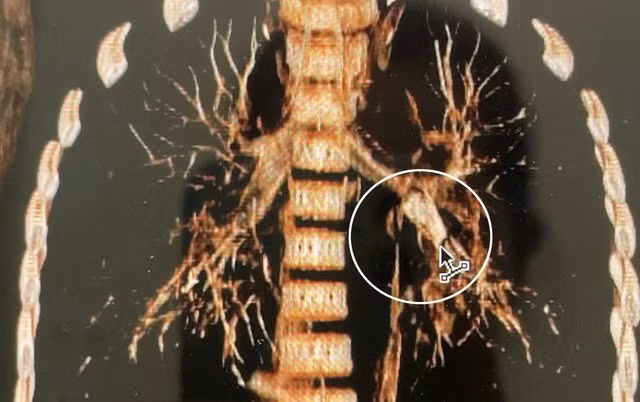

Qua thăm khám lâm sàng, các bác sĩ nghi ngờ trẻ bị hóc dị vật đường hô hấp. Kết quả chụp CT ngực ghi nhận dị vật hình ống, thành dày khoảng 1,8 mm, dài khoảng 18 mm, nằm tại phế quản thùy dưới trái, gây cản trở thông khí.

Dị vật nằm tại phế quản thùy dưới bên trái. Nguồn SKĐS